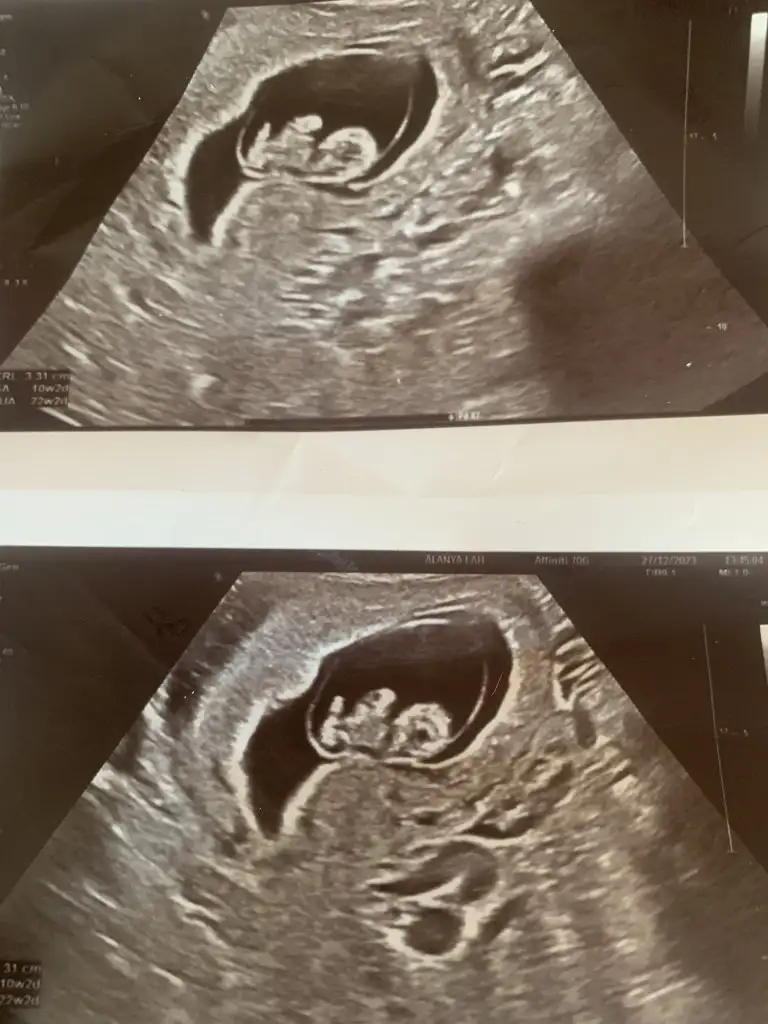

Evet benimkine bak yukarıda var resmîKeseler mi farkli anlamadim

Simdi gordum bakalim hayirlisiEvet benimkine bak yukarıda var resmî

merhabalar benim bebeğime de tahminde bulunurmuaunuz 10 haftalık tam.Prenses gibi

9 haftalıktan 12 haftalığa kadar koydum canım bende çok merak ediyorum cevabını bekliyorumSelam Kızlarbir çok kişi gruplardan beni bilir. Yine yetiştim imdatlara